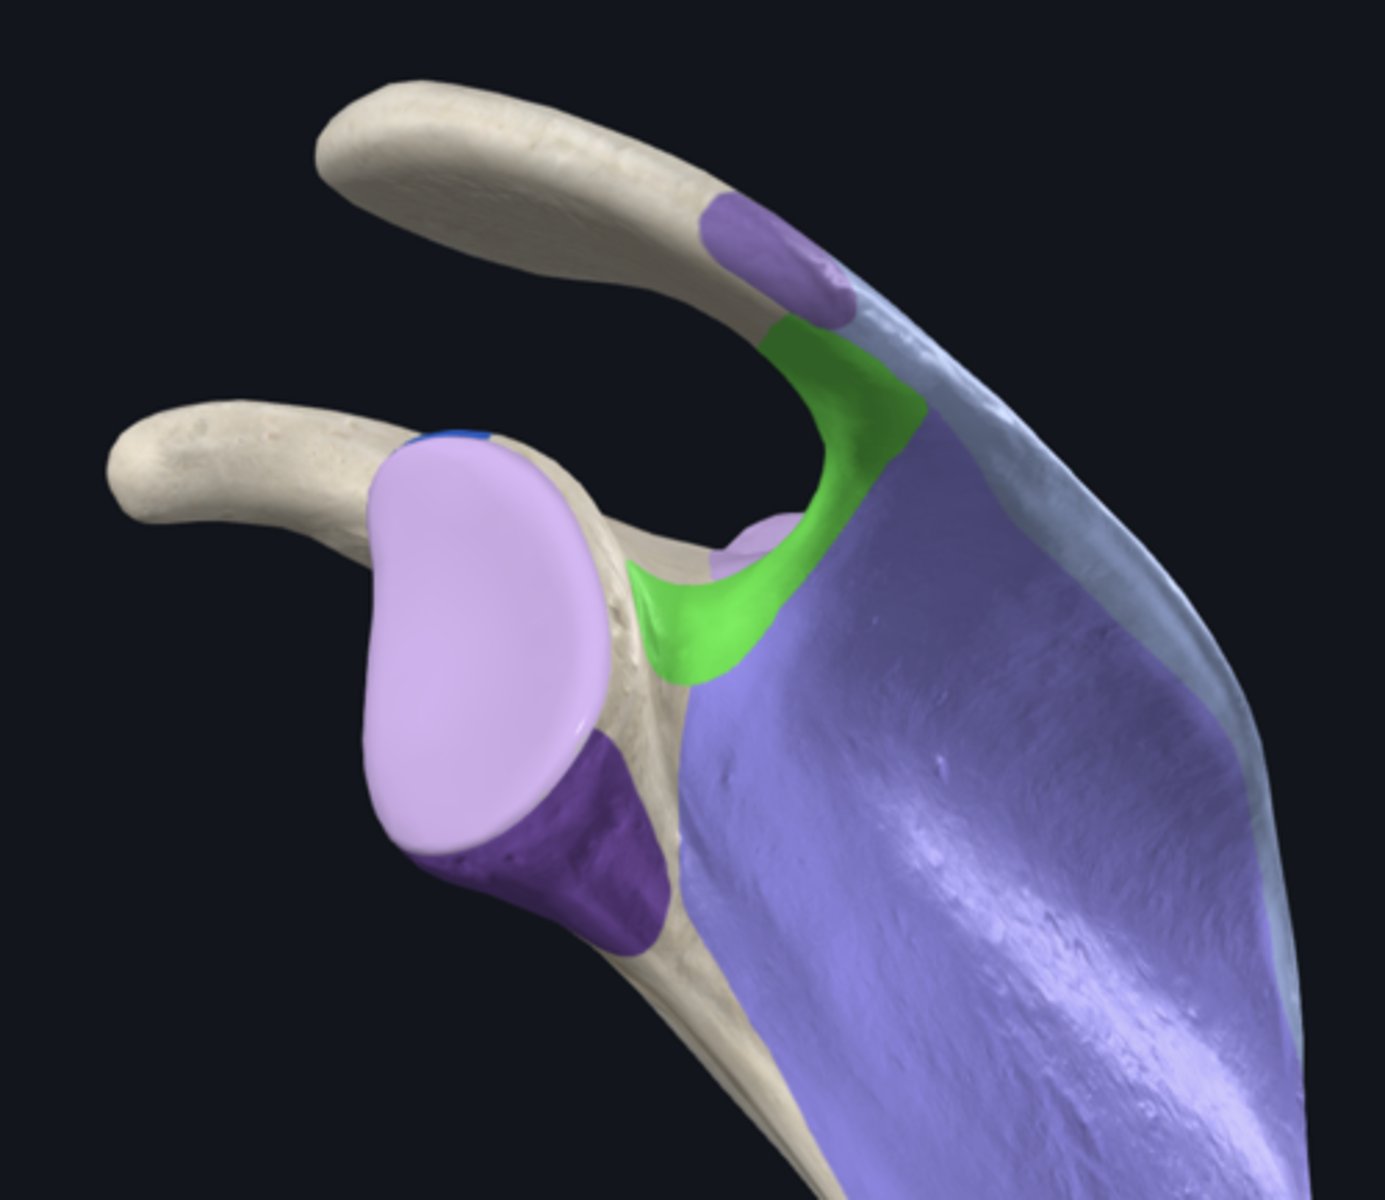

Acromion

Coracoid process

glenoid fossa

infraglenoid tubercle

spine of scapula

supraglenoid notch

supraglenoid tubercle